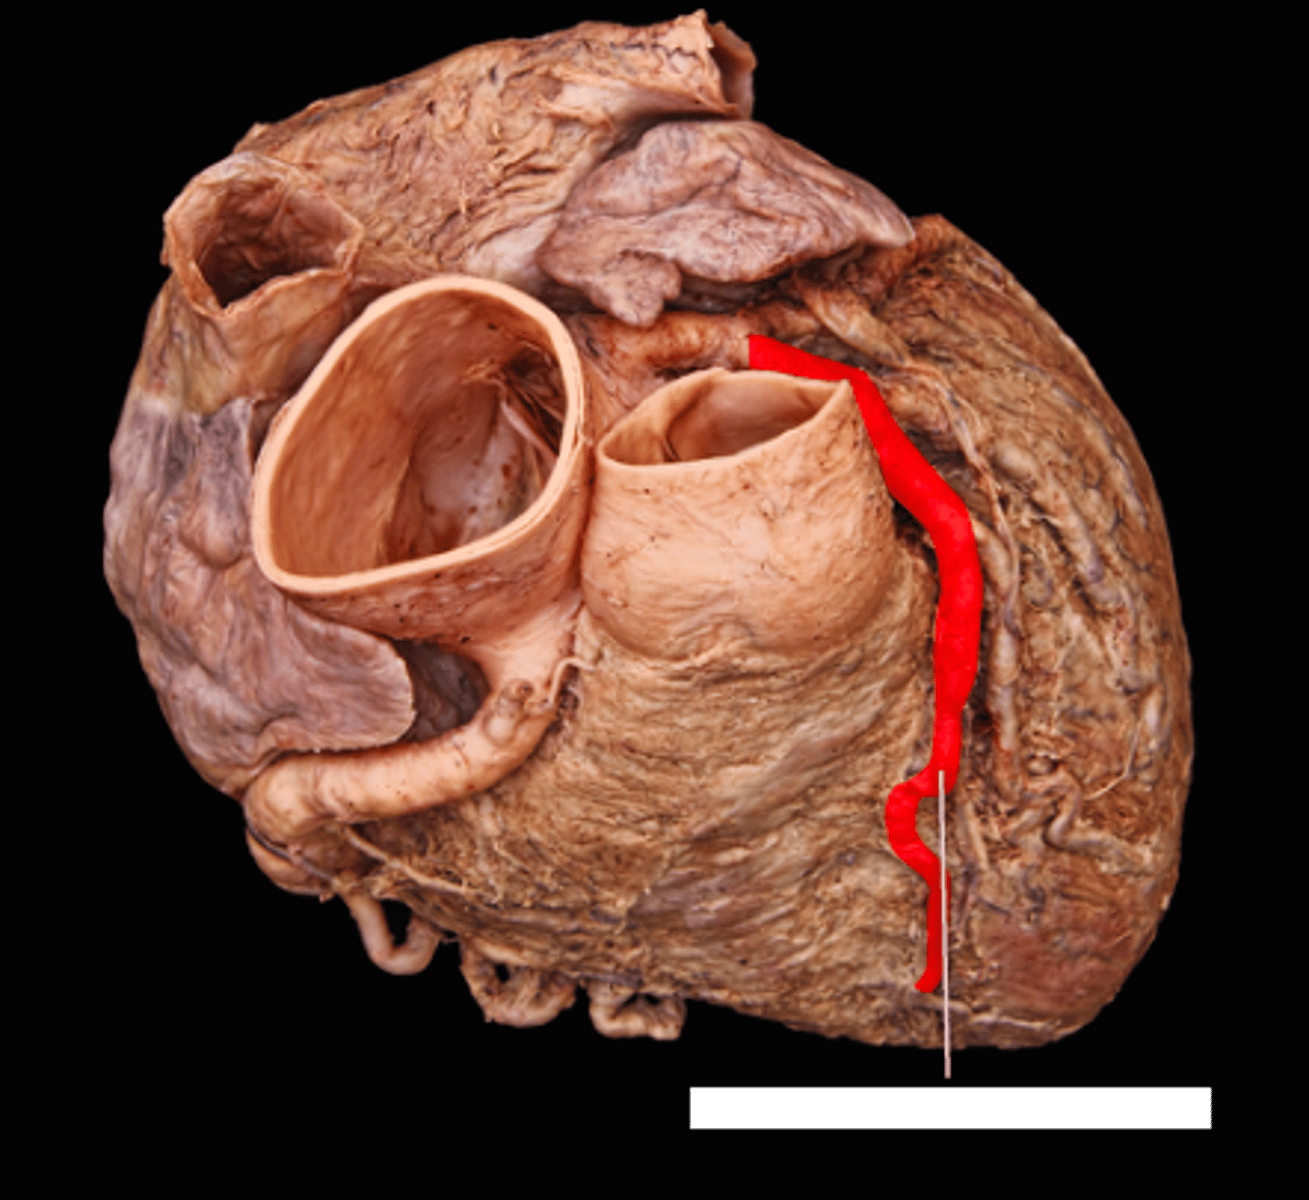

posterior interventricular sulcus

marks the boundary between the ventricles posteriorly

posterior interventricular artery

in the posterior interventricular sulcus

middle cardiac vein

middle string coming out of sinus